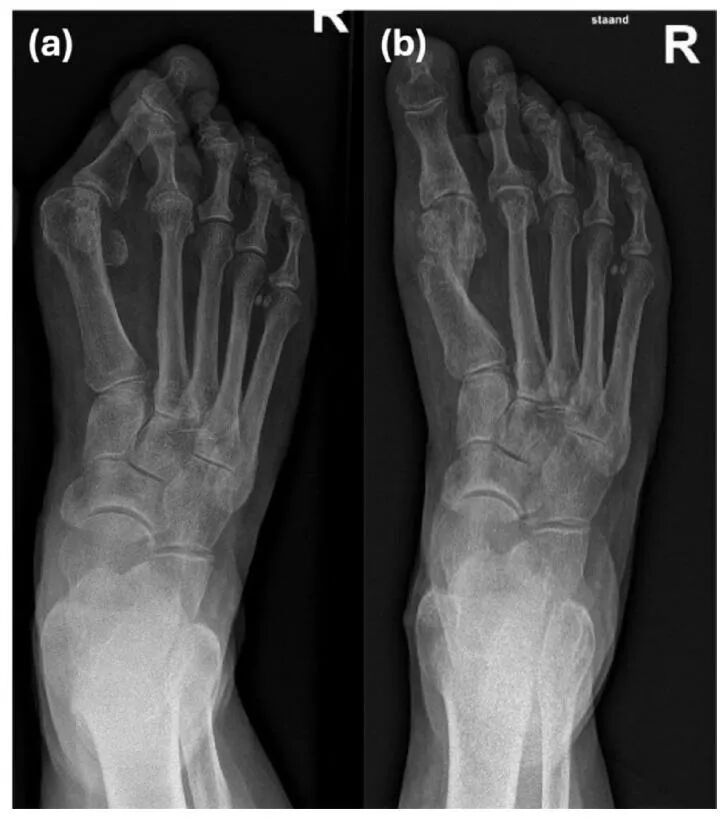

拇外翻是一种常见的、复杂的、进行性的前足畸形,具有多种临床症状和多因素病因。矫正拇外翻畸形的理想手术治疗方案仍存在争议。已有多种带或不带软组织松解的开放性骨性手术被描述,包括第一跖骨截骨术、第一跖趾关节(MTPJ)融合术或跖楔关节(MTCJ)融合术。在过去十年中,微创手术(MIS)因其临床和放射学结果与传统开放手术相当而越来越受欢迎。

无螺钉微创三平面截骨术在60岁及以上患者的拇外翻治疗中,在临床、功能和放射学方面均有显著改善。